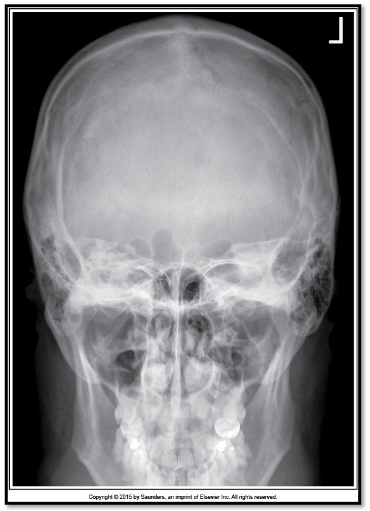

7

Q

what is the issue here

A

way too much angle

8

what is the correction

20-25 deg more caudad

lift chin to change OML by 20-25 deg